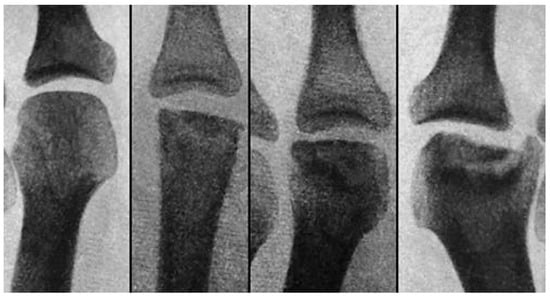

Figure 13.

The radiographic progression of the second metatarsal head osteochondrosis in a 22-year-old female patient who had not received any treatment.